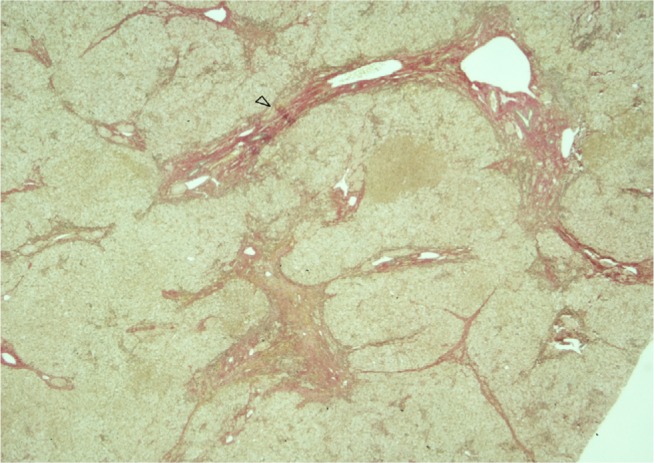

Abstract Image